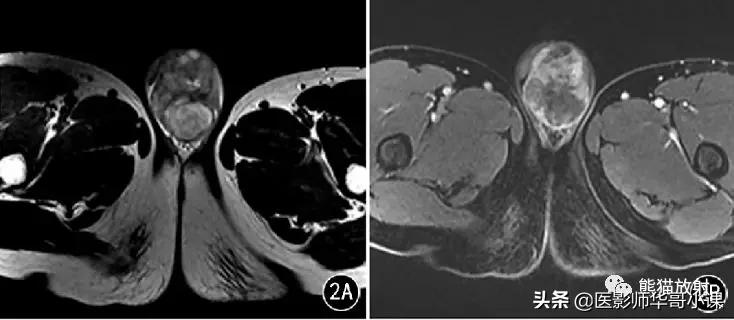

图1 男,32岁, 右侧*丸睾**精原细胞瘤 。T2WI示右侧*丸睾**肿物,其内见低信号纤维分隔及稍高信号出血灶;增强分隔明显强化,且高于肿瘤实质。